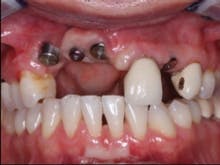

FIG. 2 — Impression copings in place showing lack of adequate gingiva and bone, as well as difficult angulation of implant placement.

In my opinion, when the implants have been placed in positions that make the prosthodontic treatment difficult, custom abutments are almost always necessary (Fig. 2). As you observe the angulation of the impression copings, it is evident that the implants are approximately 45 degrees from optimum placement angulation. The practitioner placing these implants had to either place them at the angulations that are evident, or graft significant bone into the potential implant locations before placing the implants. I feel that the decision not to graft was appropriate, assuming that the lab technician making the prosthesis is highly competent. This much angulation deviation often makes splinting the crowns together the most advisable treatment, since forces on the implants will be at angles not in line with the long axis of the implants, and any additional strength that can be obtained in the prosthesis is certainly advisable.